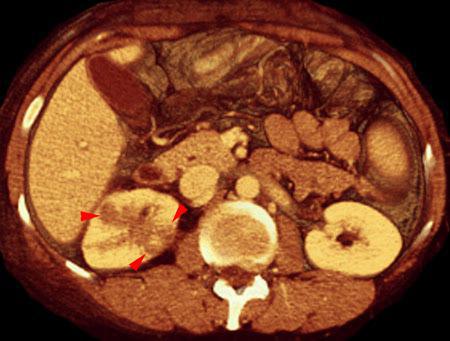

VR seccional. Visión axial caudal. TC contrastado en fase venosa poniendo de manifiesto múltiples focos hipodensos (puntas de flecha) que traducen una pielonefritis multifocal